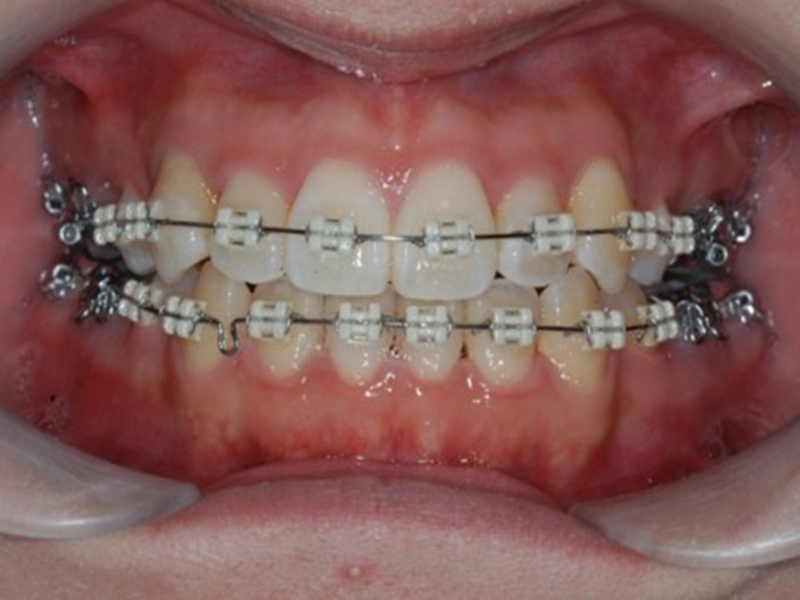

経過